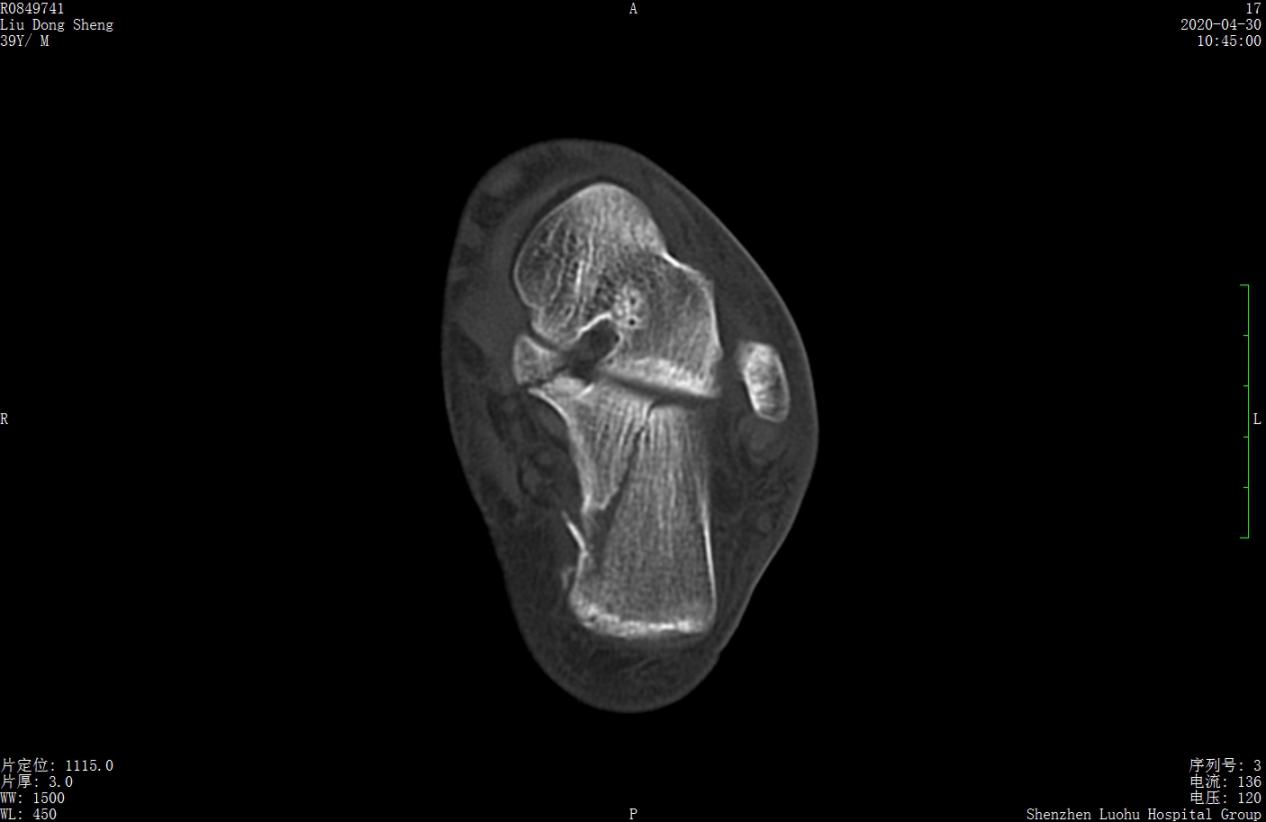

案例1影像

术前CT示跟骨严重粉碎骨折,移位明显